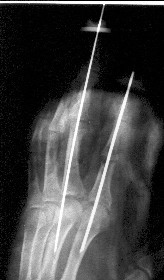

Уважаемые коллеги, в травмотделение БСМП Ангарска поступил пациент с отрывом 3 пальца на уровне проксимального межфалангового сустава (дистальная

часть пальца висит на кожном лоскуте с латеральной стороны пальца шириной 1 см, повреждены сухожилия сгибателей и разгибателей), многооскольчатым переломом головки основной фаланги 2 пальца, рваной раной в проекции сустава, превышающей половину диаметра пальца (сухожилия целы)(снимок 1, снимок 2). Выполнена ПХО ран, МОС спицами трансартикулярно (снимок 3, снимок 4). При обсуждении тактики лечения возникли разногласия между врачом, выполнявшим ПХО, и заведующим. Зав. отделением считает, что выбранная тактика неверна, и необходимо было после проведения ПХО сделать вытяжение типа Черкес-Заде за пальцы. Просим высказать присутствующих свое мнение о выполненной операции и о дальнейшей тактике лечение больного. Заранее спасибо.